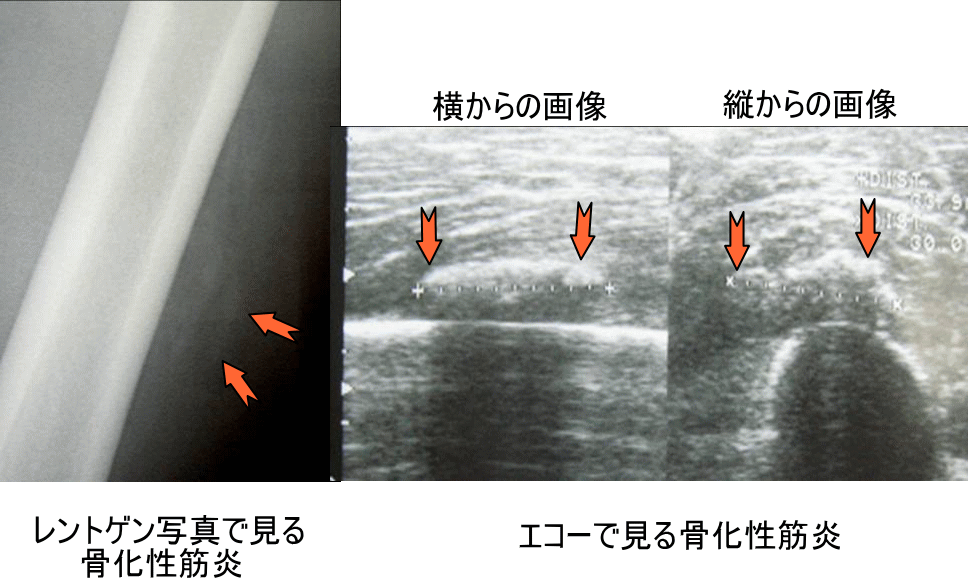

特に重度のチャーリーホースの場合は上図のように血腫が大腿骨付近に形成されるため修復過程で骨化が生じ、骨化性筋炎という状態になることがあります。(打撲の後に膝がなかなか曲がらない、筋肉が突っ張って痛いなどの症状は骨化性筋炎が疑われます。)